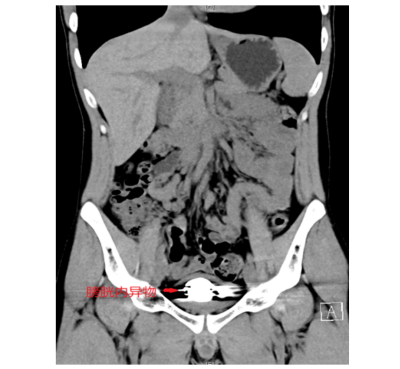

据了解,22岁的简轩(化名)因尿频、尿急、尿痛持续一年,近期症状加重才前往香港马会app (南华大学附属香港马会app )泌尿外科就医,经影像学检查发现,其膀胱内竟积聚大量直径约5毫米的金属圆珠,排列紧密且表面已形成钙化外壳。该院泌尿外科一区主任傅发军及其团队结合病史及临床经验判断异物为数十颗磁性钢珠,如不及时取出,长期滞留可能导致尿路梗阻、感染甚至组织损伤。

由于异物数量多、磁性强且表面光滑,传统开放手术创伤较大,团队研究后决定采用“经尿道膀胱镜钬激光碎石取异物术”。手术需克服三大难点:磁珠相互吸附难以分离、表面光滑不易抓取、膀胱壁脆弱易损伤。医疗团队通过精准影像定位和精细操作,历时2小时成功取出全部异物,共计50颗磁性钢珠。术后患者症状立即缓解,恢复顺利。